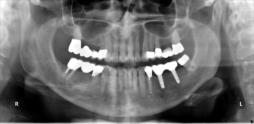

Beispiele für komplexe implantologische Versorgungen aus unserer Gemeinschaftspraxis

(Planung / Endversorgung -- als Röntgenaufnahmen)

C2